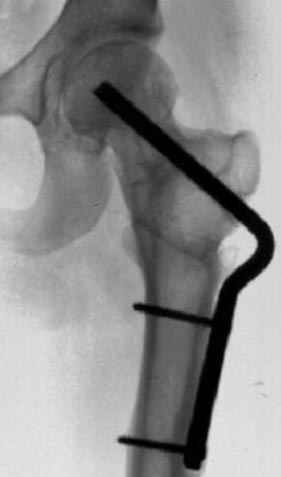

Если, например, доводится лечить больных с псевдартрозами шейки бедра, то надобность есть, и приходится. См. приложение.

На рисунке N1 предоперационный план лечения ложного сустава шейки бедра- линия ложного сустава, угол и направление введения импланта, клиновидная остеотомия в градусах и миллиметрах, второй снимок после коррекции, расчет, на сколько удлиняется конечность и размеры импланта;

N3 рисунок окончательный снимок, после операции моя рентгенограмма должен выглядеть примерно как эта картина. На N4 снимке клин перед удалением; N5 послеоперации 3 нед.; N6 окончательная рентгенограмма.

варус при проксимальном отделе 95 градусной пластиной.